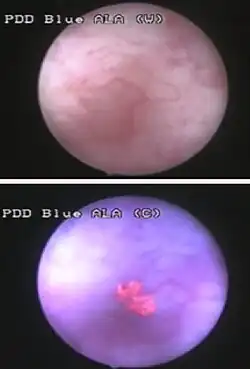

Those suspected of having bladder cancer undergo several tests to assess the presence and extent of any tumors. The gold standard is cystoscopy, wherein a flexible camera is threaded through the urethra and into the bladder to visually inspect for cancerous tissue.[6][7] Cystoscopy is most efficient at detecting papillary tumors (tumors with a finger-like shape that grow into the urine-holding part of the bladder); it is less efficient with small, low-lying carcinoma in situ (CIS).[8] CIS detection is improved by blue light cystoscopy, where a dye (hexaminolevulinate) that accumulates in cancer cells is injected into the bladder during cystoscopy. The dye fluoresces when the cystoscope shines blue light on it, allowing for more accurate detection of small tumors.[6][8]